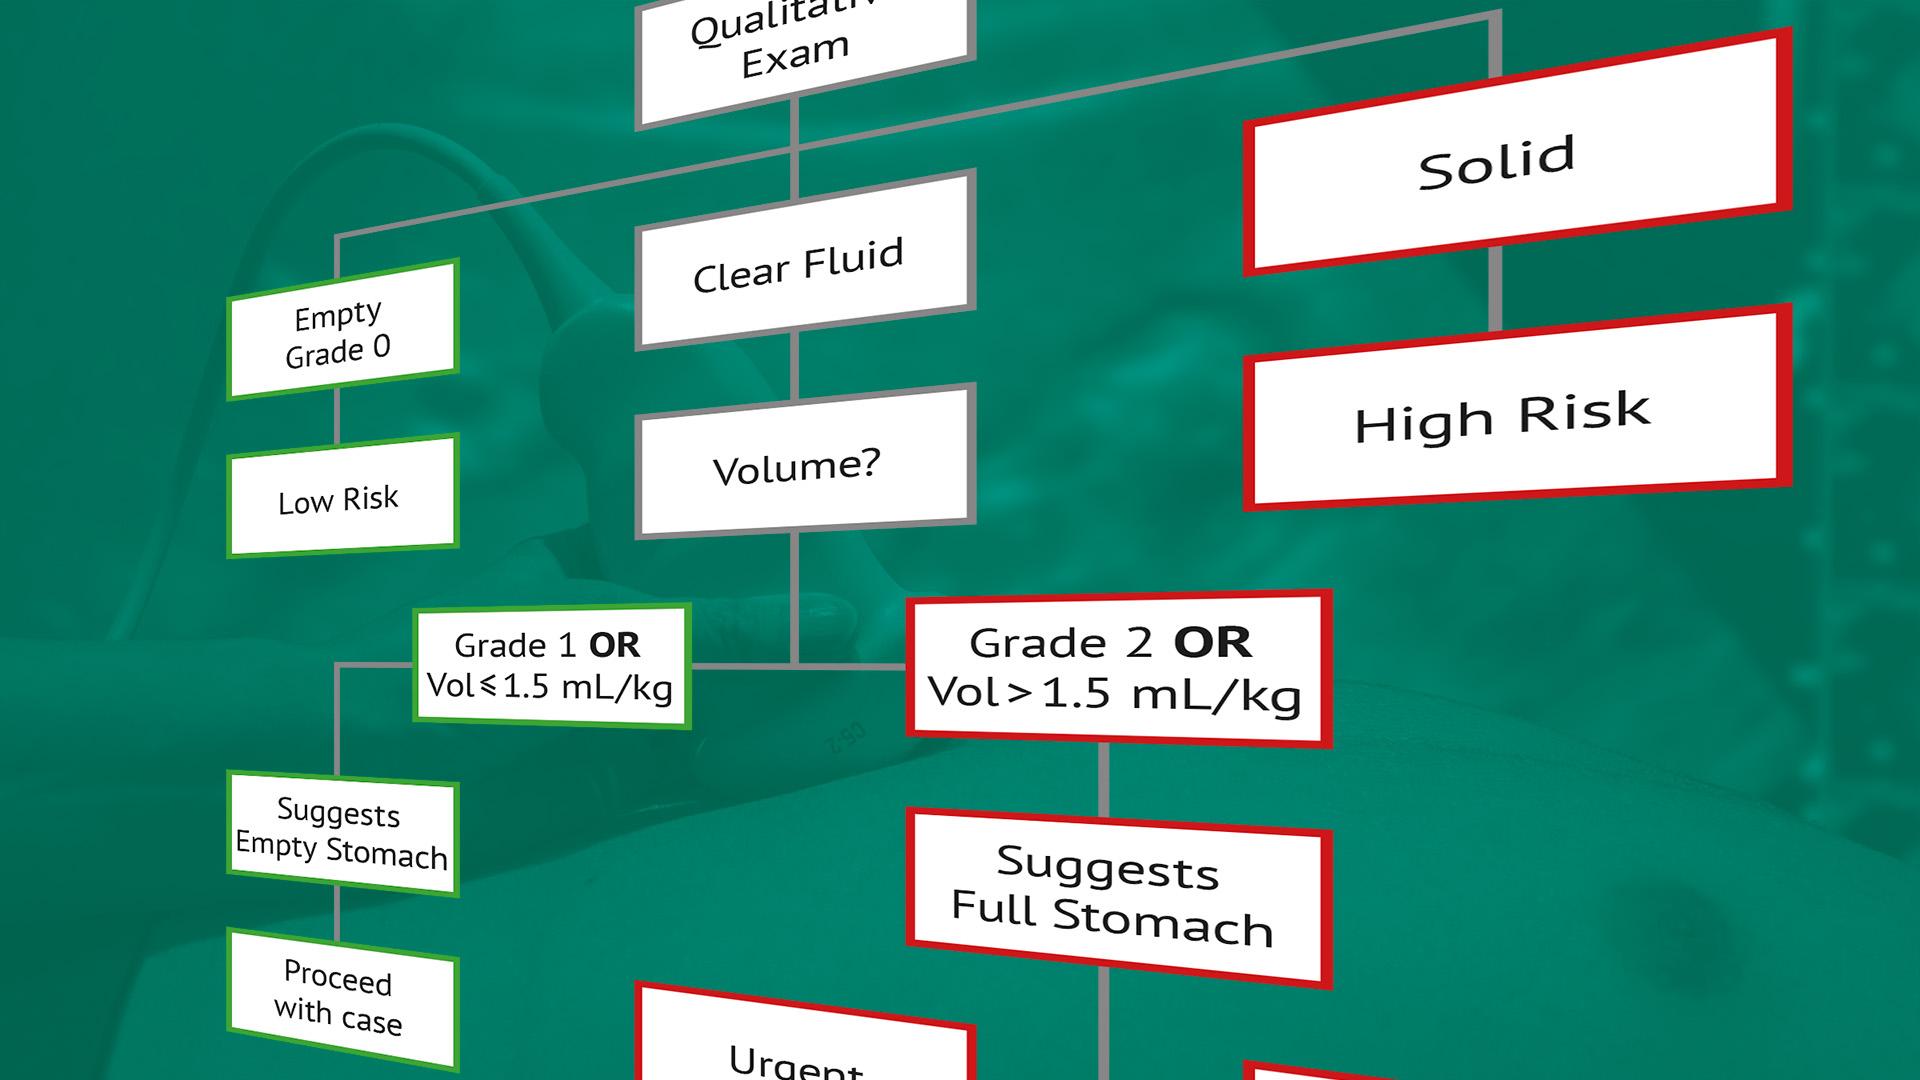

De opleiding bestaat uit vier stappen (zie curriculum).

Hierbij volgen wij de systematiek van het I-AIM model dat stapsgewijs verwerven van PoCUS-skills bevordert. I-AIM staat voor ‘Indication, Acquisition, Interpretation, and clinical decision-Making’